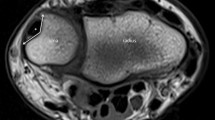

The RUG angles are measured in the axial view. While the coronal and sagittal planes may not be moved, the axial plane is adjusted in the coronal view according to the defined measurement locations. Measurement locations (Fig. 2a) are the middle of the height of the ME (M1), the most proximal location in the ulnar groove (M3), middle of the distance between M1 and M3 (M2), and the most distal location on the ME.

Retrocondylar ulnar groove angle measurements. Measurement locations are adjusted in the coronal view (a) by locating the middle of the medial epicondyle (M1), the most proximal point in the ulnar groove (M3), the middle between M1 and M3 (M2), and the most distal point on the medial epicondyle (M4). The corresponding axial view for M1 (b), M2, (c), M3 (d), and M4 (e) are shown including the location of angle measurement (*). Blue line: sagittal plane; red line: axial plane; green line: coronal plane. Orange lines: distance measurements serving the location of M1 and M2

Angle measurements are conducted between two lines connecting the angular point which is the deepest (most volar) point of the RUG in the axial view with the lateral and medial transitions from a concave to a convex shape (Fig. 2b–e).